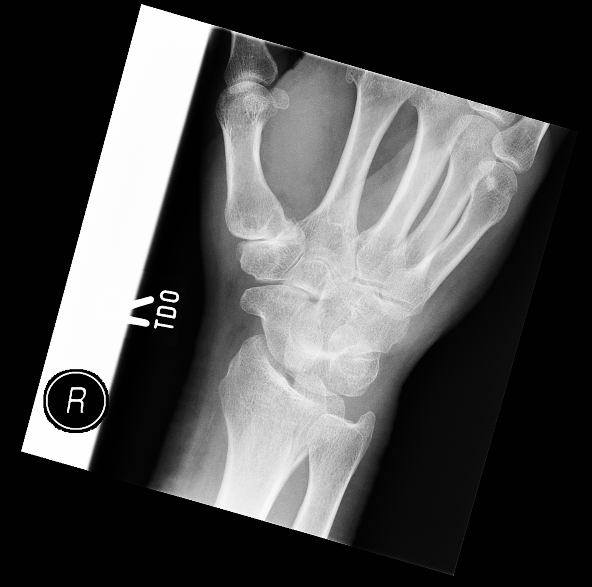

| 30 |

Abnormal fr hamate |

Abnormal Right hamate and fourth metacarpal base fractures |

Correct |